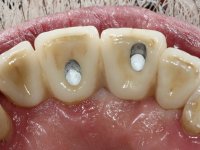

Segunda Fase

6 meses após a colocação da ponte, o paciente sofre um novo traumatismo comprometendo a viabilidade dos dentes 1.2 e 1.1. Foi realizada uma prótese removível acrílica para reabilitar provisoriamente o paciente enquanto foram extraídos os dentes 1.2 e 1.1 e foi colocado o implante no local do dente 1.1. Passados 3 meses foi realizada uma impressão ao implante colocado no 1.1 e simultaneamente foi feito um arrasto da ponte dos dentes 2.1 e 2.2. Para esse efeito no implante 2.1 foi utilizado um parafuso de uma peça de transferência. Dessa forma conseguiu-se impressionar corretamente a arquitetura gengival do sector antero-superior. O objetivo era simultaneamente impressionar corretamente esta zona e aproveitar a estrutura metálica desta ponte para confecionar a nova ponte de 4 elementos. Foi colocado um parafuso de cicatrização no implante 2.1 e foram acrescentados os dentes 2.1 e 2.2 na prótese removível. Com perícia laboratorial foi criada uma nova infraestrutura metálica de 4 elementos assente nos implantes 1.1 e 2.1 e com os elementos pônticos suspensos 1.2 e 2.2. No implante 2.1 manteve-se a conexão interna ao implante no implante 1.1 optou-se por uma peça intermédia facilitando a inserção da infraestrutura. A nova infraestrutura foi verificada em boca. Como pode ter havido alguma alteração da arquitetura gengival com a remoção da ponte e colocação do parafuso de cicatrização no 2.1, foi feita uma chave de silicone para permitir uma impressão de arrasto da infraestrutura metálica. Uma nova gengiva artificial foi realizada no modelo de trabalho de acordo com esta impressão de arrasto. Foi colocada cerâmica de tonalidade coronária e gengival. A peça protética foi aparafusada lentamente em boca para permitir uma adaptação dos tecidos moles. Após o correto assentamento e verificação imagiológica a ponte foi definitivamente apertada em boca e os orifícios de acesso obturados. Independentemente dos infortúnios que o paciente teve, pude ter a satisfação de o ver contente com esta reabilitação.